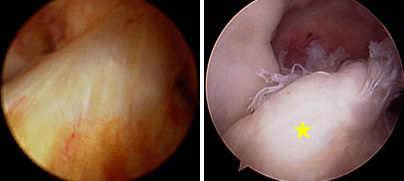

(Left) Arthroscopic picture of the normal ACL. (Right) Arthroscopic picture of torn ACL [yellow star].